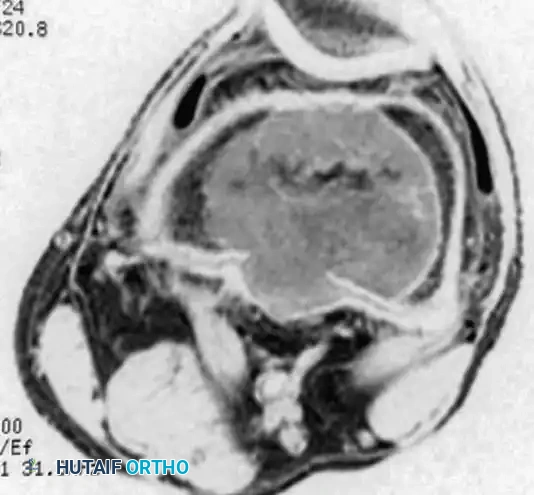

MRI is indispensable for determining the exact intraosseous extent of the tumor, evaluating the integrity of the subchondral bone, and identifying soft-tissue extension.

Axial MRI of the same distal femoral lesion, highlighting cortical thinning and the precise intramedullary boundaries of the tumor.

- Signal Characteristics: The lesion typically demonstrates low-to-intermediate signal intensity on T1-weighted images and heterogeneous high signal intensity on T2-weighted images.

- Secondary Aneurysmal Bone Cyst (ABC): MRI is highly sensitive for detecting fluid-fluid levels, which are indicative of a secondary ABC—a phenomenon occurring in up to 20% of GCT patients.